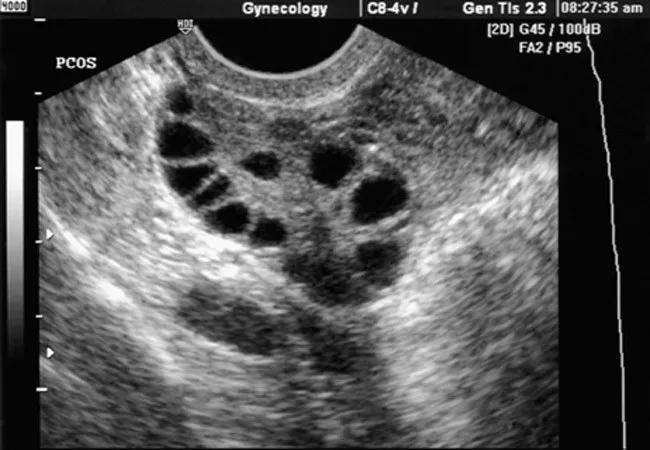

The most common cause of anovulation in North America is polycystic ovarian syndrome (PCOS) — a metabolic disorder with a primary reproductive manifestation. The term PCOS is a misnomer: there are no cysts in the classic gynecologic sense. Rather, the ovary has many subcapsular follicles smaller than 10 mm with increased thecal and stromal tissue.

Ultrasound of the ovaries of a woman with polycystic ovary syndrome.